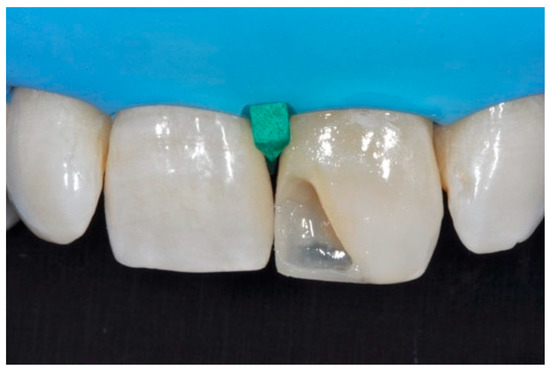

Figure 23.

Frame is completed with interproximal matrices. Reprinted from Restauri diretti nei settori anteriori, G. Paolone, S. Scolavino, © 2021, with permission from Quintessence Publishing Italy.

Figure 24.

Frame is corrected with the help of diamond burs. Reprinted from Restauri diretti nei settori anteriori, G. Paolone, S. Scolavino, © 2021, with permission from Quintessence Publishing Italy.